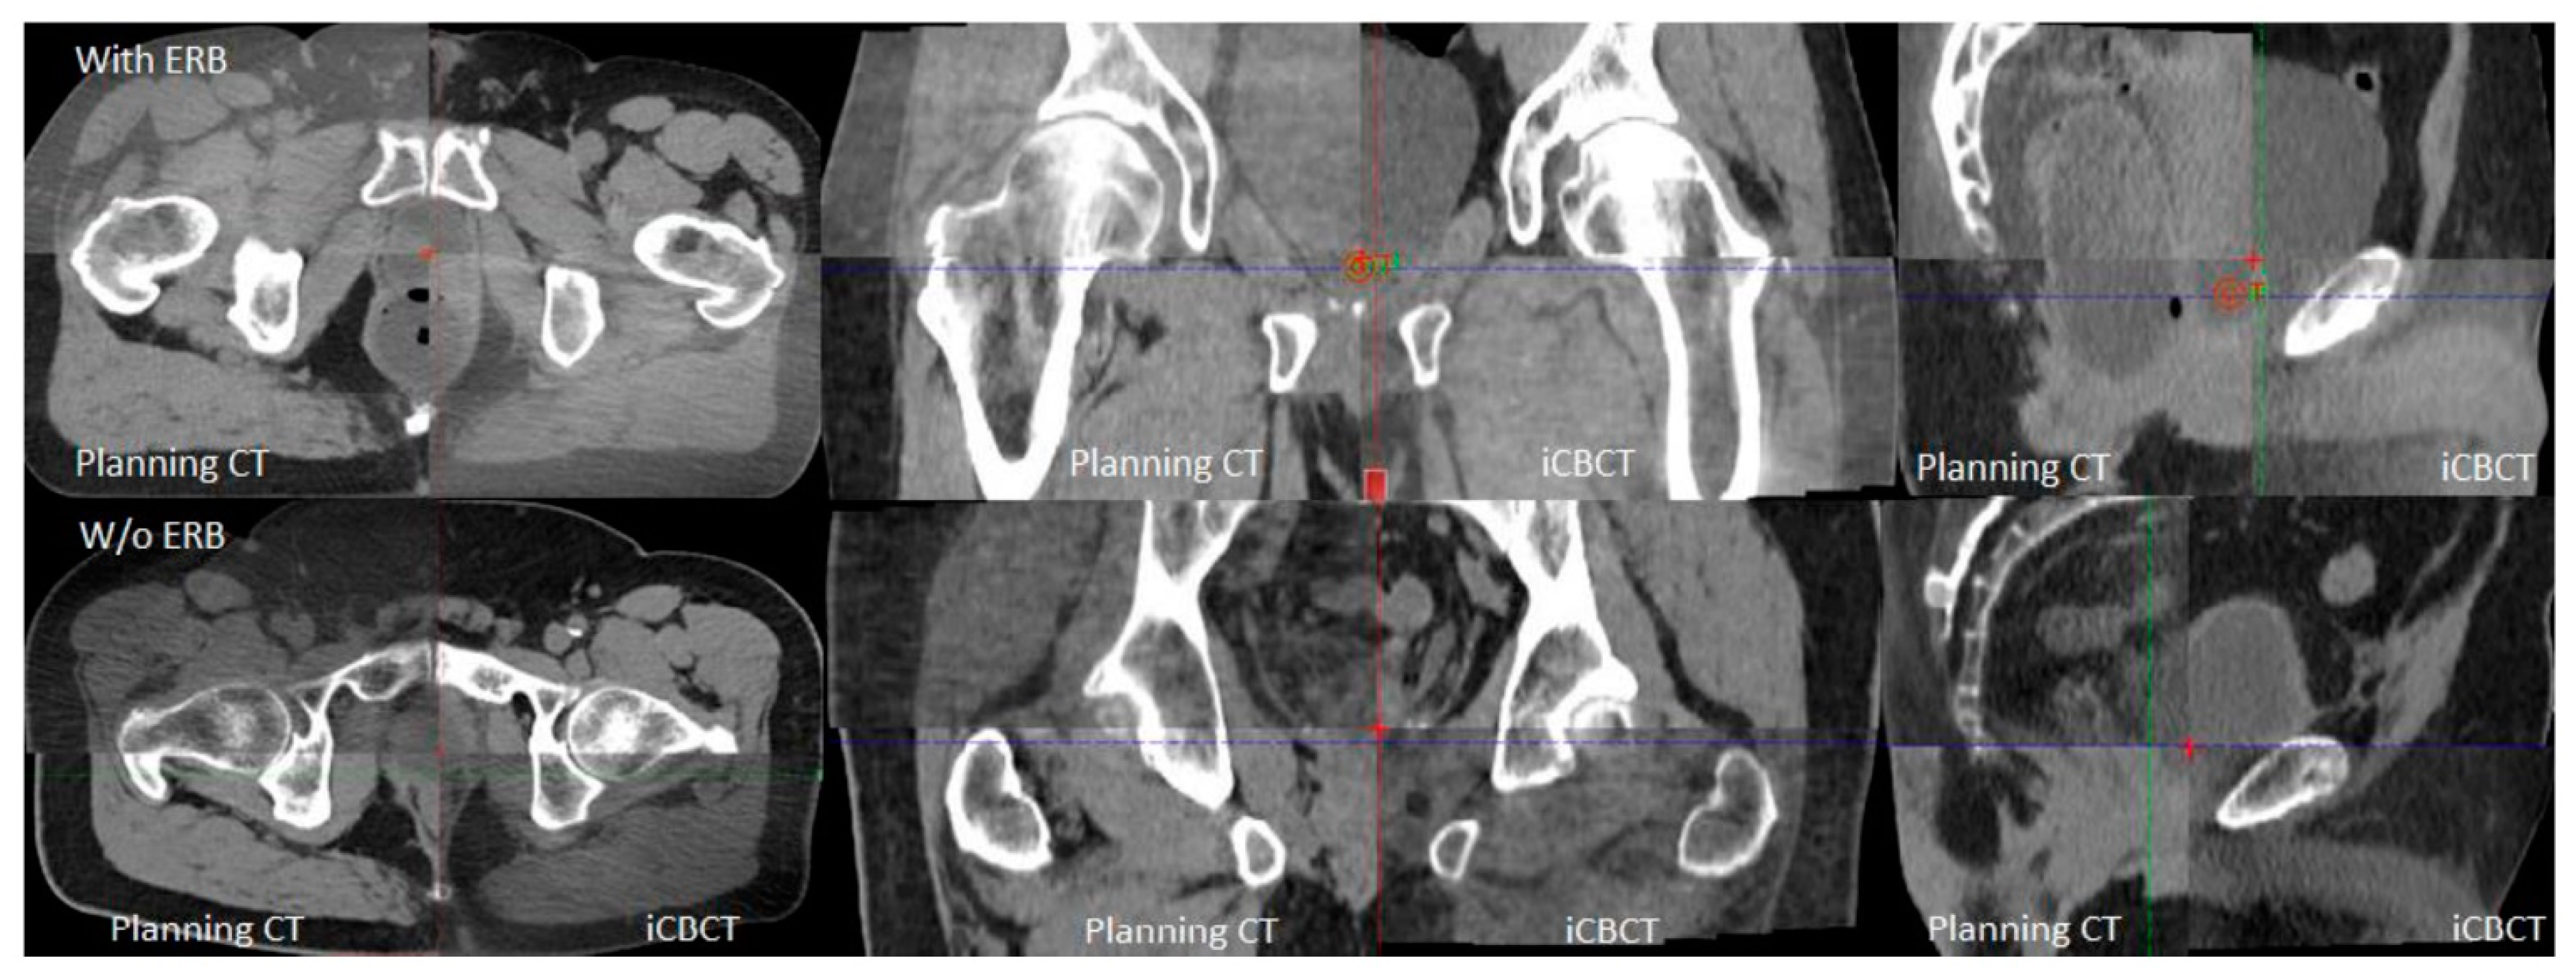

- Kim, Y.S.; Joo, J.H.; Kim, Y.J.; Cho, Y.P.; Lee, H.Y.; Jeong, C.Y.; Kwak, J.; Cho, B.C. Analysis of prostate bed motion using an endorectal balloon and cone beam computed tomography during postprostatectomy radiotherapy. OncoTargets Ther. 2016, 9, 3095–3100. [Google Scholar] [CrossRef]